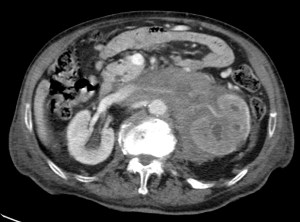

CASO 2: Paciente de 68 años con dolor en flanco izquierdo, fiebre y malestar general. A la exploración existe enrojecimiento de la piel con sensación de masa palpable y puño percusión muy positiva.

El paciente es alégrico al Iodo. Se realiza TC sin contraste para ampliar estudio.

Todos estos hallazgos están en relación con una Pielonefritis Xantunogranulomatosa que afecta al riñón derecho junto con una colección que ha fistulizado a región lumbar.

- Pielonefritis Xantunogranulomatosa.

- Es una forma infrecuente de pielonefritis crónica, de origen obstructivo, caracterizada por la formación de un absceso granulomatoso que puede extenderse al EPR-, severa destrucción renal y un cuadro clínico de fiebre, malestar general, dolor en el flanco y masa renal, a veces palpable.

- En placa simple podía verse un masa que renal con o sin borramiento de la línea del psoas. En ecografía, cálculos y aumento del tamaño renal en la forma difusa con múltiples áreas anecoicas correspondientes a las colecciones purulentas.

- Los hallazgos en TC pueden ser:

- Uni o bilateralidad de la lesión.

- Afección difusa o localizado.

- Litiasis de tipo coraliforme, calcificaciones intraparenquimatosas.

- Aumento difuso del tamaño renal.

- Áreas hipodensas o hipoecogénicas dentro de la lesión renal debidas a cálices dilatados, abscesos o áreas de necrosis parenquimatosa.

- Pobre o nula eliminación del medio de contraste en el riñón afectado.

- Compromiso inflamatorio que excede los límites del riñón y genera colecciones periféricas o extensión hacia vísceras vecinas.